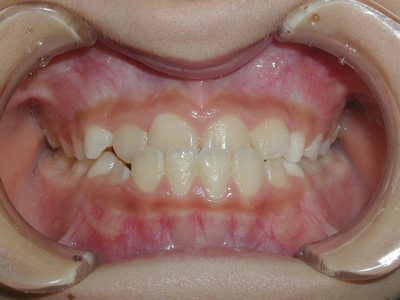

上顎の劣成長 (成長不足) による反対咬合で、上顎は拡大装置と上顎前方牽引装置を併用し前方方向への成長を促して前歯の咬み合わせを改善した後に、上下顎の前歯をマルチブラケット装置で並べました。治療の期間は2年でした。

1期治療終了時

2期治療終了時